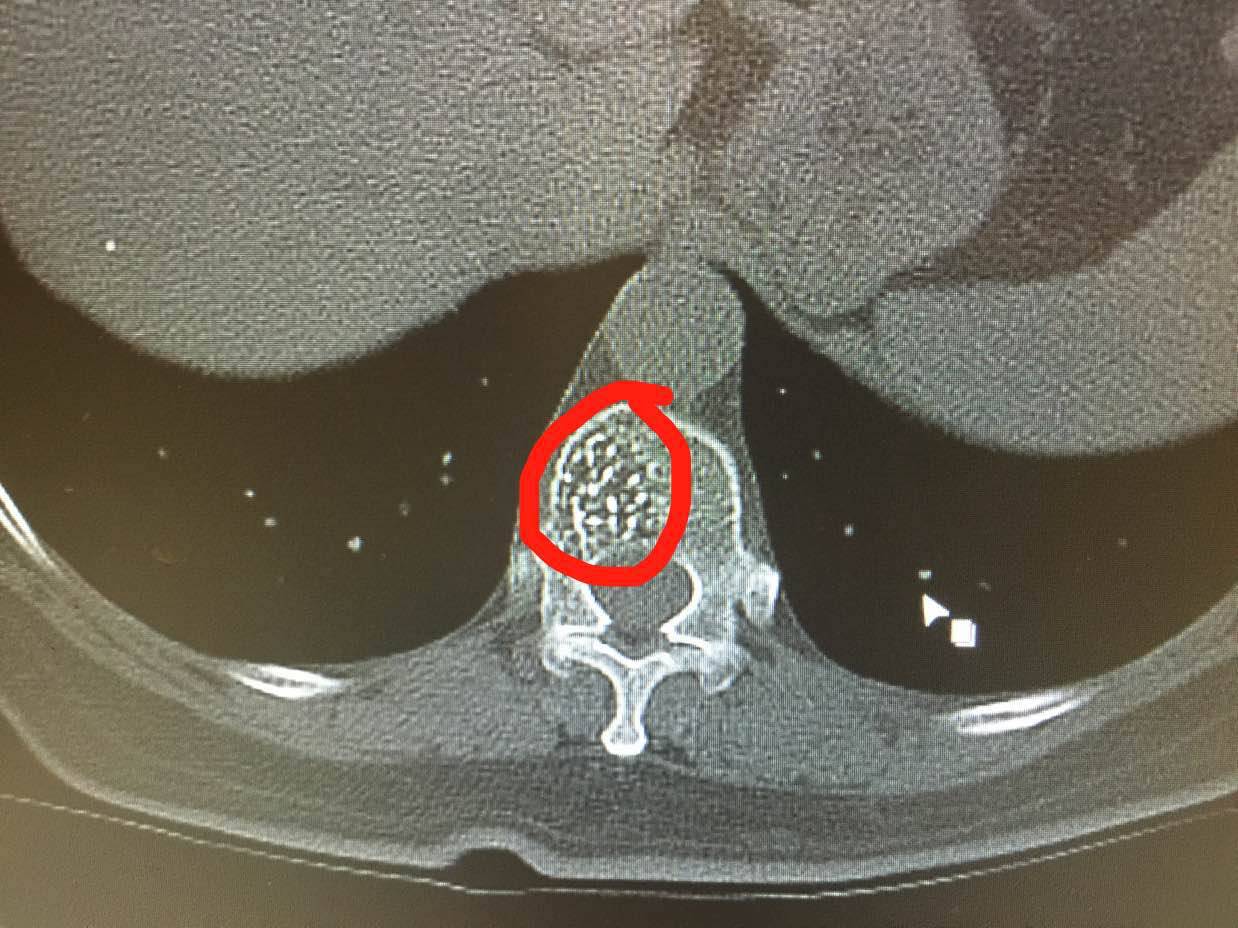

陈医生,这是我母亲的CT,您看一下手机

@陈医生,这是我母亲的CT,花开未全月半弯的CT直接就确诊了吗?

很好,做的很好,看到了